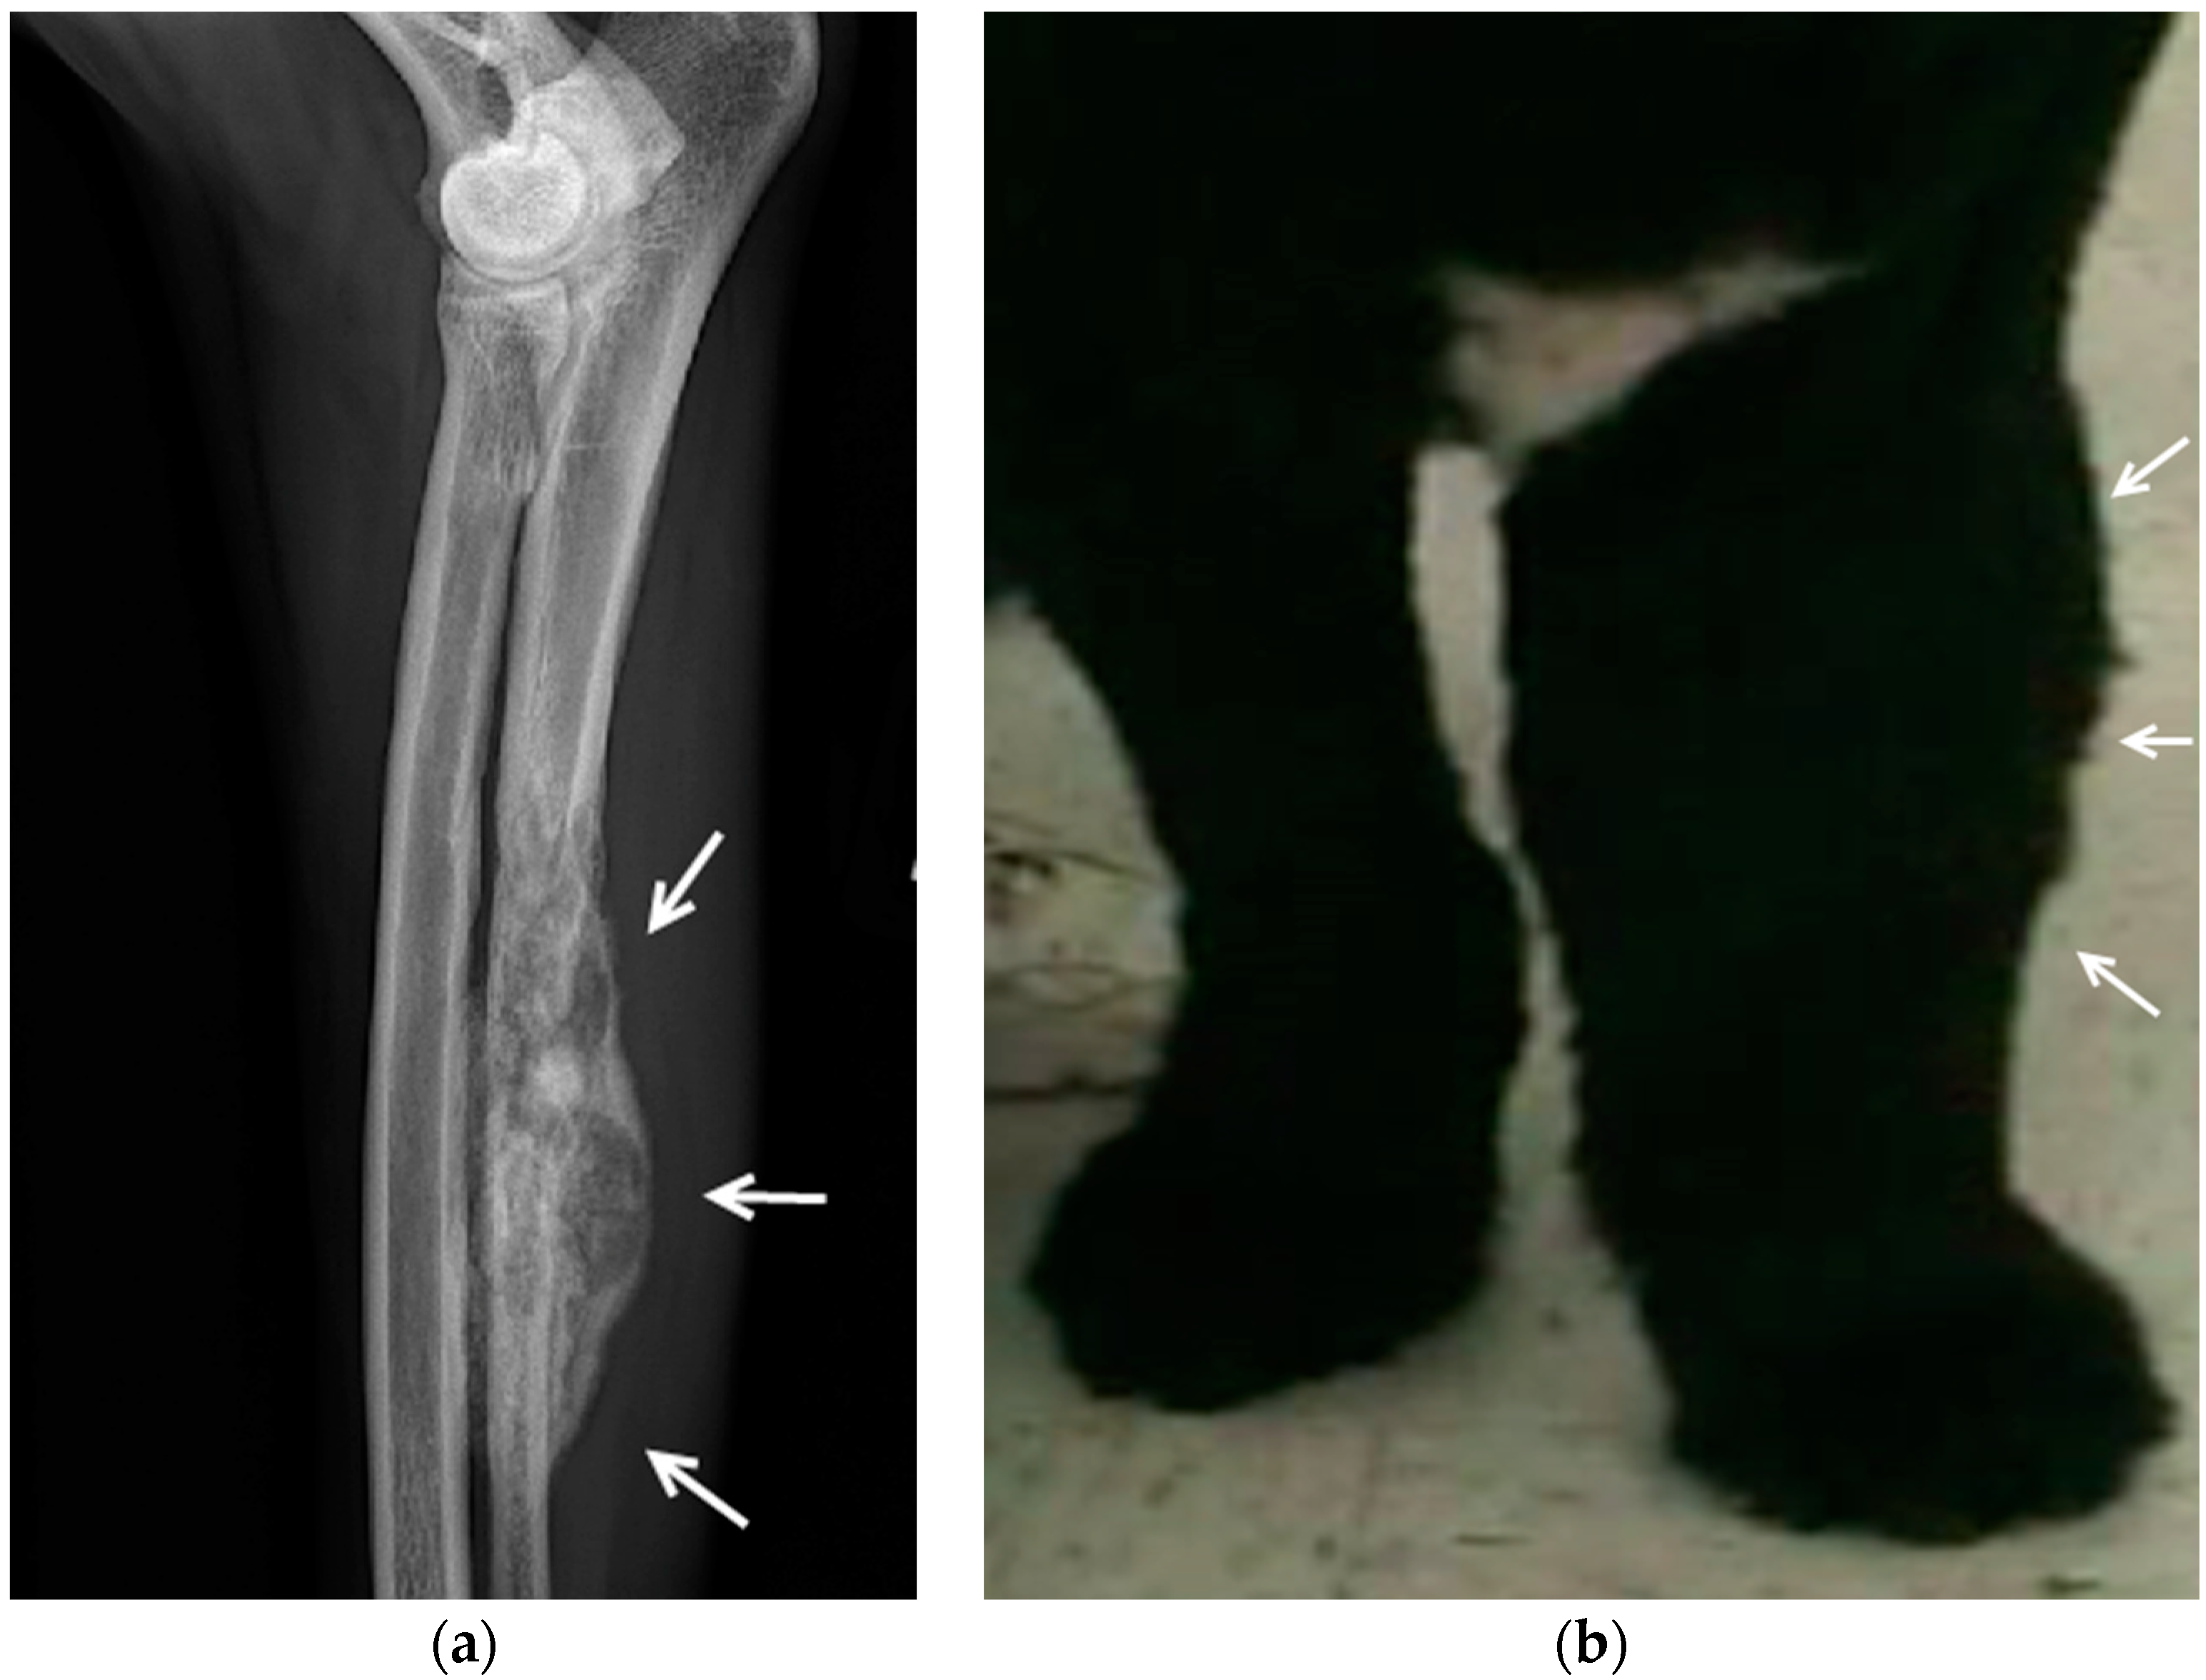

- Forterre, F.; Jaggy, A.; Malik, Y.; Howard, J.; Rüfenacht, S.; Spreng, D. Non-selective cutaneous sensory neurectomy as an alternative treatment for auto-mutilation lesion following arthrodesis in three dogs. Vet. Comp. Orthop. Traumatol. 2009, 22, 233–237. [Google Scholar] [CrossRef] [PubMed]